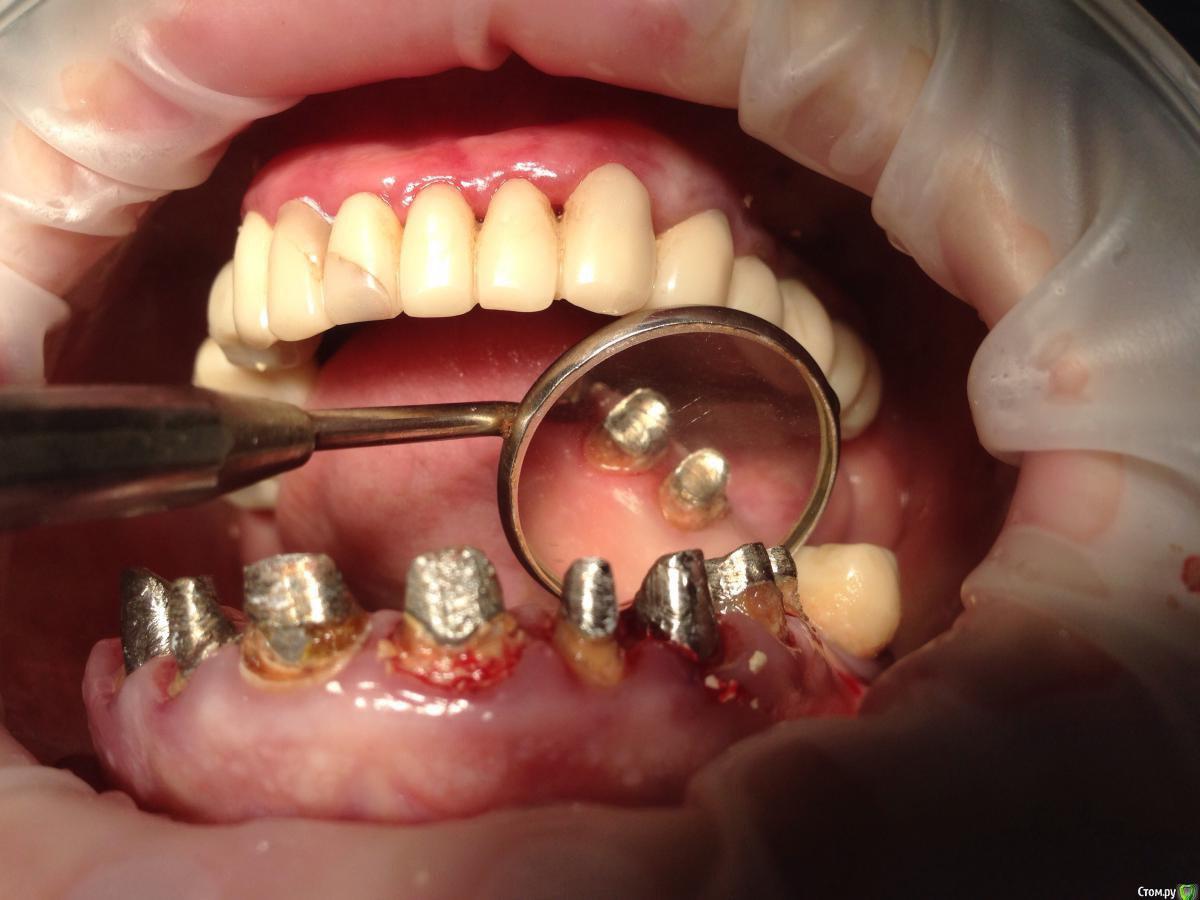

Bratok Опубликовано 17 июля, 2016 Поделиться Опубликовано 17 июля, 2016 Коллеги, всем привет! Вот такая пациентка в клинике был доктор у нас с 20 летним стажем, она уехала сейчас и не работает. Протезировала пациентку.. Были изготовлены временные коронки.. Судя по всему страдал герметизм и под ними все печально.. Десне и феррулу хана...Чтобы Вы тут посоветовали? Планировалось к нее мк... Сделать в 3 сегмента 3-3 и остальные блоком. Какой прогноз? Лет 5? Извиняюсь за качество rg.. Ссылка на комментарий

AndyAndy Опубликовано 17 июля, 2016 Поделиться Опубликовано 17 июля, 2016 Привет! М-да, печаль беда.... Мы же с вами понимаем что все это надо извлекать, убирать кариес и смотреть на то что останется. Возможно хир удлинение коронковой части. Пациентка как настроена вообще? вы наверняка объяснили ей чем она рискует. Но все- таки стремно так все оставлять. Там герметизм нарушен и между вкладками и стенками канала, 100%. Ссылка на комментарий

korotkevich Опубликовано 17 августа, 2019 Поделиться Опубликовано 17 августа, 2019 (изменено) Коллеги, всем привет! Вот такая пациентка в клинике был доктор у нас с 20 летним стажем, она уехала сейчас и не работает. Протезировала пациентку.. Были изготовлены временные коронки.. Судя по всему страдал герметизм и под ними все печально..Десне и феррулу хана...Чтобы Вы тут посоветовали?Планировалось к нее мк...Сделать в 3 сегмента 3-3 и остальные блоком. Какой прогноз? Лет 5?Извиняюсь за качество rg..В идеале доставать вкладки, убирать кариозные ткани, делать билдапы и затем либо хирургическое удлинение, либо вертипреп, либо и то, и другое; и металлокерамические коронки с гирляндой, таким образом сохраните максимально то, что есть Изменено 17 августа, 2019 пользователем korotkevich Ссылка на комментарий